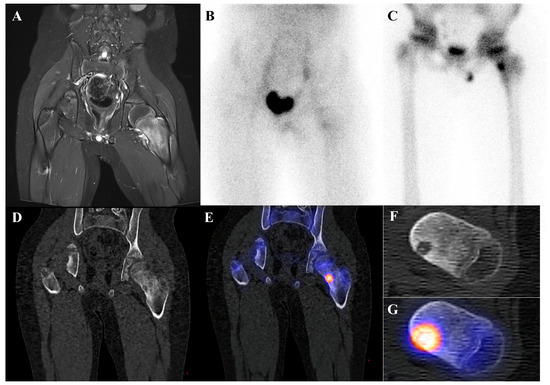

Clinical, Radiological, and Pathological Features of Intraosseous Hibernoma: A Systematic Review of Case Reports and Case Series

Intraosseous hibernoma (IOH) is a rare benign tumor composed of brown adipose tissue within the bone, frequently mimicking metastatic lesions and leading to diagnostic challenges. This systematic review aimed to consolidate and analyze all published IOH cases to improve recognition and inform management. [...] Read more.

Intraosseous hibernoma (IOH) is a rare benign tumor composed of brown adipose tissue within the bone, frequently mimicking metastatic lesions and leading to diagnostic challenges. This systematic review aimed to consolidate and analyze all published IOH cases to improve recognition and inform management. A comprehensive literature search was conducted in PubMed, Web of Science, Scopus, Google Scholar, and the Cochrane Library from database inception to March 2025. Studies were eligible for inclusion if they reported histopathologically confirmed cases of intraosseous hibernoma (IOH) in human patients. A total of 62 cases from 30 studies were included. The mean age was 59.2 years, with a female predominance. Lesions were most frequently located in the pelvis and spine and were typically identified incidentally during cancer staging or imaging performed for unrelated indications. Imaging often revealed sclerotic patterns on computed tomography (CT), hyperintense signals on magnetic resonance imaging (MRI) T2-weighted and short tau inversion recovery (STIR) sequences, and mild to moderate uptake on 18F-fluorodeoxyglucose positron emission tomography/computed tomography (18F-FDG PET/CT). Immunohistochemistry consistently showed S100 protein positivity. Most patients underwent biopsy and were managed conservatively, with no cases of malignant transformation reported. IOH is a benign entity with distinctive radiologic and immunohistochemical features that may mimic malignancy. Awareness of its presentation can reduce misdiagnosis and unnecessary interventions, supporting biopsy-based confirmation and conservative management in most cases. Full article